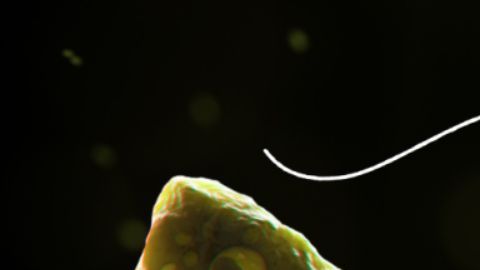

Ameba come-cerebros

Representación generada por computadora de Naegleria fowleri en varias etapas. Crédito: CDC | Cortesía